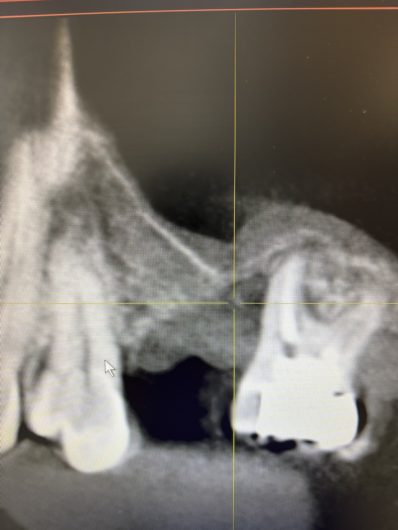

左上(レントゲン上なので逆です)の一本歯を失った所にインプラントを埋入予定ですが、インプラントを埋める所に骨が数ミリしかありません。このままでは鼻腔(上の黒い部分)に突き抜けてしまいインプラントを埋める事が出来ません。

サイナスリフトという手技を駆使してインプラントを埋める場所に顆粒状の材料を入れて厚みと幅を作りました。おおよそ6〜8ヶ月後には完全な骨になります。